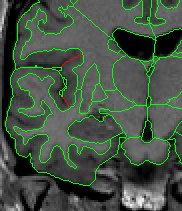

The insular cortex is “hidden” between the temporal and inferior parietal corticies. By drawing sulci lines in the sagittal view, we gain an outline of it in the coronal. Choose a sagittal slice where insula is clearly visible (Fig 1), then draw a “circle” around it (Fig 2). Do this for several slices and for both hemispheres.

Figure 1              Figure

2

Once you have drawn your sulci lines, the insula should be clearly outlined (by little dots) in the coronal view (Fig 3). This is particularly useful in the more anterior slices.

Figure 3